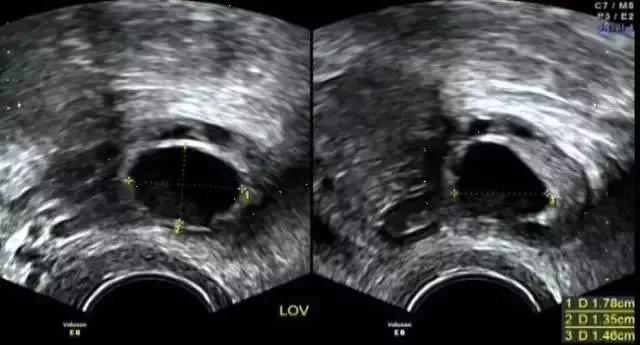

再进一步成为优势卵泡(>15mm),

最终成为成熟卵泡(>18mm),

卵泡>18mm时:为成熟卵泡,此时可诱导排卵